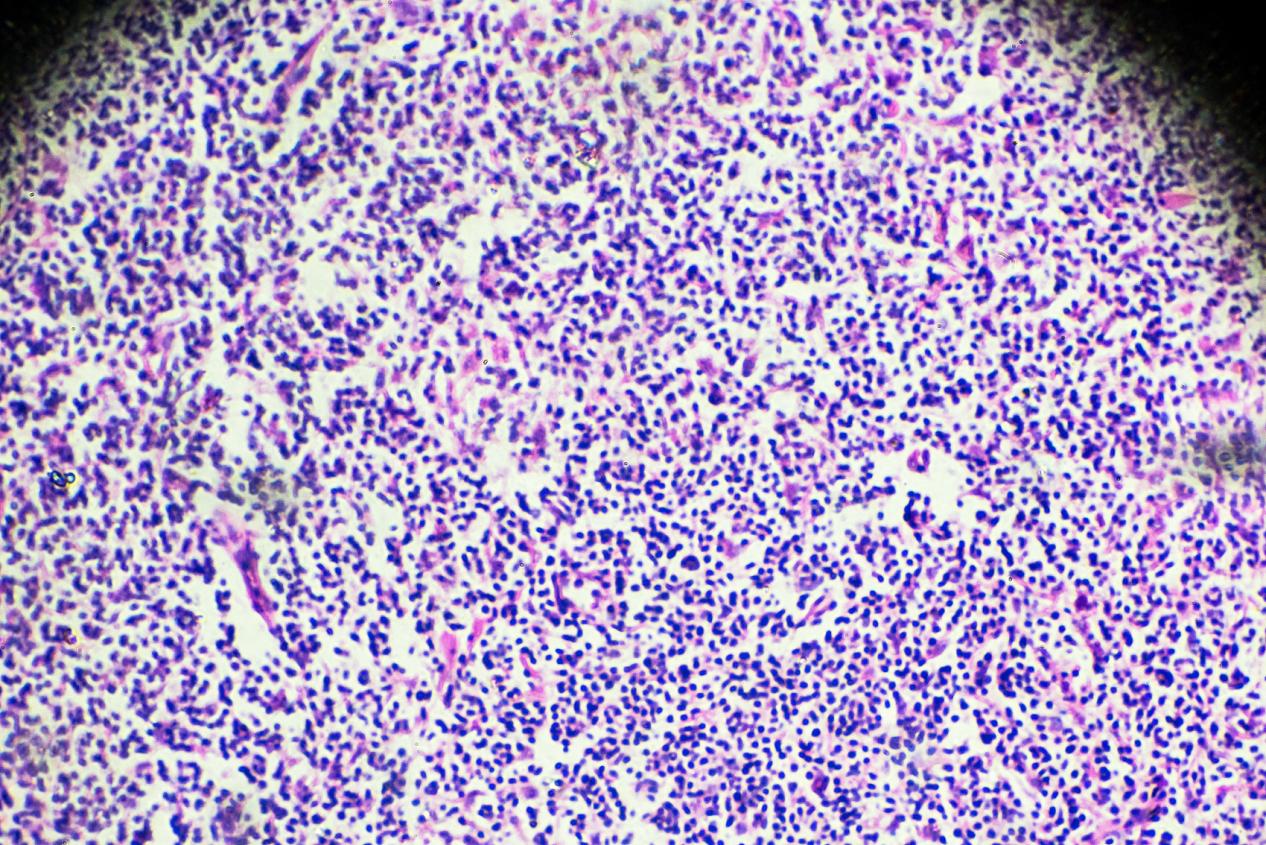

淋巴瘤的临床表现,昆明淋巴瘤医院哪家好-昆明医科肿瘤医院淋巴瘤是一类以淋巴细胞或淋巴组织为起始细胞的肿瘤,其临床表现因患者年龄、病理类型和病变部位等因素而异。以下是淋巴瘤可能出现的一些常见临床表现:淋巴结肿大:淋巴结是淋巴组织的一部分,淋巴瘤的最常见表现之一是...

淋巴瘤的概述,昆明淋巴瘤医院推荐哪家-昆明医科肿瘤医院淋巴瘤是一种源于淋巴系统的恶性肿瘤,它可以发生在身体任何部位的淋巴组织,包括淋巴结、脾脏、骨髓和其他淋巴器官。淋巴瘤是一种比较常见的肿瘤,它可以发生于任何年龄,但是在中年人和老年人中更为常见。淋巴瘤是由淋巴...

淋巴瘤的发病机制,昆明淋巴瘤医院排名哪家好-昆明医科肿瘤医院淋巴瘤是一种由淋巴细胞或浆细胞发生恶性转化导致的恶性肿瘤。淋巴瘤的发病机制是一个复杂的过程,涉及到多种因素的相互作用。本文将介绍淋巴瘤发病的几种常见机制。染色体异常染色体异常是淋巴瘤发生的常见机制之一...

淋巴瘤的病因,昆明淋巴瘤医院哪家好-昆明医科肿瘤医院淋巴瘤是一种由淋巴细胞或浆细胞发生恶性转化导致的恶性肿瘤。目前对于淋巴瘤的具体病因仍不是完全清楚的,但是已知有一些可能的因素会增加淋巴瘤的发生风险。免疫系统异常:免疫系统的异常功能可能会导致淋巴细胞的不正常增...